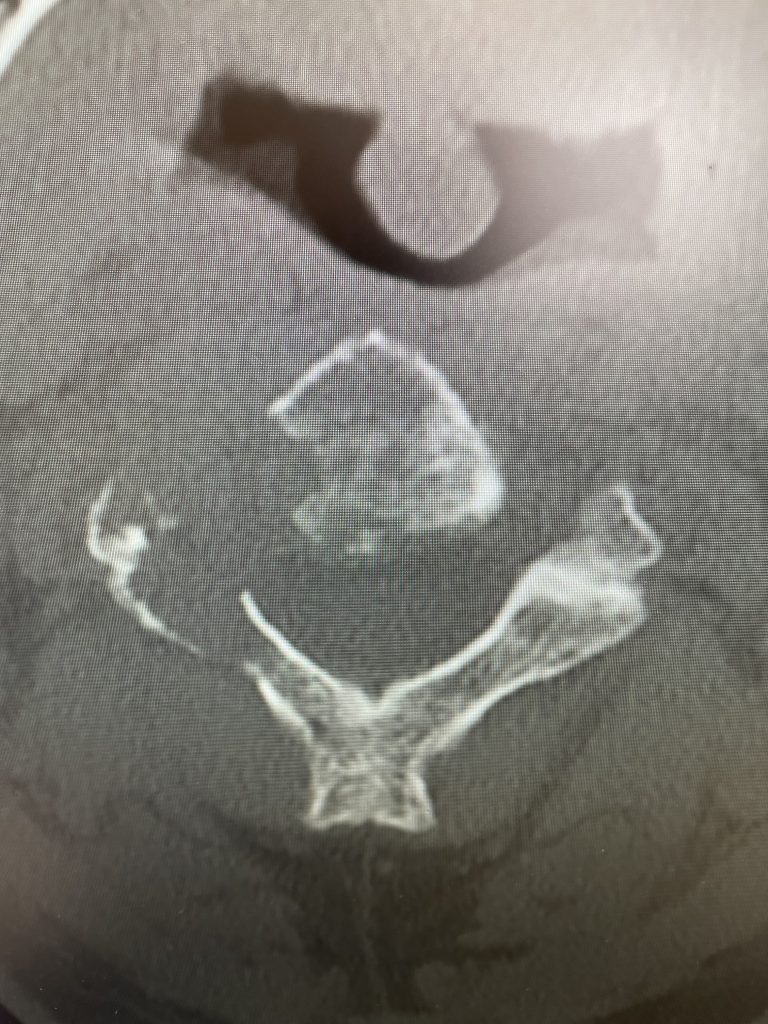

After several months he represented with worsening neck pain and placed in a hard collar. He had a repeat CT scan which showed some progression of disease now more affecting the C3 vertebral body (Fig 11). The patient had flexion extension x-rays which showed stability. The patient was referred to pain management for better control. He was placed in a hard collar. Given the progression of disease after radiation, three columns of the spine affected, progression of neck pain, potential for collapse of the bone and retropulsion into the canal causing quadriplegia, surgical stabilization was offered to the patient. Given the poor bone quality, as one can assume that the multiple myeloma could extend to other adjacent bones, it is challenging to stabilize the patient with good fixation. Options would include stabilizing with hardware and fusion from C1 to C5 which would provide stabilization above and below the area of potential collapse. Another option would be to go from occiput to C5. This is a more morbid procedure and really severely limits head movement. Your “yes” and “no” movements are between your occiput and C2. Most people do not realize that sixty percent of your head and neck motion is between the occiput and C2. The rest is distributed amongst the other cervical vertebrae. If a fusion was carried up to C1, then the patient would not lose as much motion not to mention the significantly increased exposure and risk with an occipital-cervical fusion. The patient declined surgical treatment at this point knowing all the risks. He agreed to wear his collar. He was in better pain control. He will be followed closely.

Fig 2: Sagittal CT scan demonstrating progression of disease into C3 vertebral body